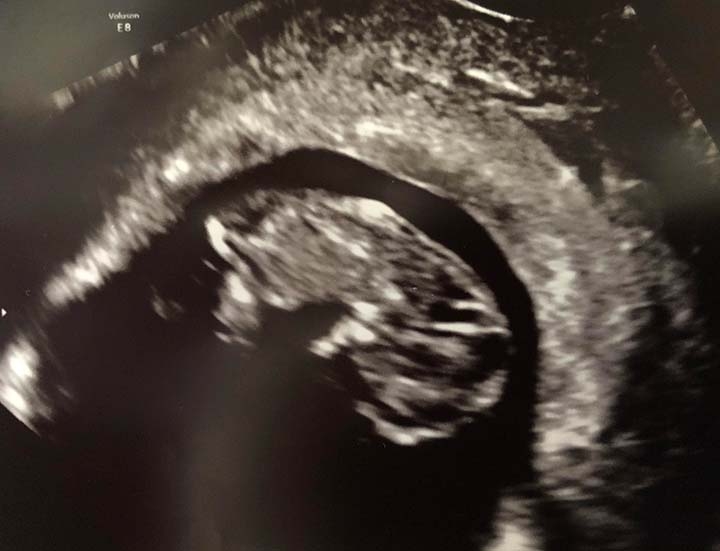

Hi everyone, 6 weeks ultrasound. I’m scheduled back for an 8 weeks ultrasound. Doctor said it’s twins but one is smaller than the other one that we had to wait and see if the other progresses. Has anyone had a similar situation? This is my 3rd pregnancy but first time twins.